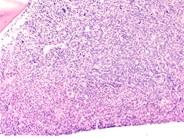

The intersect of the normal and leukemic marrow areas are evident at the higher magnification shown. Increased but scattered blasts can be seen in the area of normal hematopoiesis.